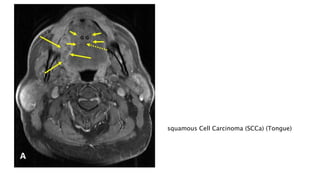

The document outlines the diagnosis of squamous cell carcinoma, detailing methods such as biopsy, imaging studies, and histopathological examination. It emphasizes the importance of tissue samples and various imaging tests to determine the cancer's size and spread. The focus is particularly on cases involving the oral cavity, including the tongue.